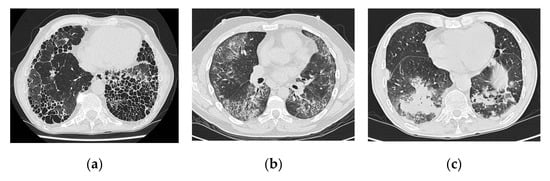

4.2. Imaging